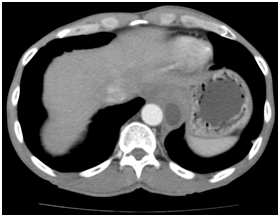

Mr T.A, aged 46, living in Bangui (Central African Republic) is consulted to emergencies for recurrent epigastric pain and dysphagia lasting for five months in a slimming context. This patient has a history of chronic alcohol abuse. He presented the clinical examination, impaired general condition (8kg / 5 months), a lack of palpable mass in the abdomen. In exploring this pain, abdominal ultrasound showed diffuse punctate calcifications in the entire pancreas, normal pancreatic duct, cystic mass in finely particulate content, lobulated epigastric 103mmde of major axis in cross section. It rises towards the tail of the pancreas and comes in contact with the heart. This mass was a very individualized wall without color Doppler signal. Chest X-ray showed fluid density mass, homogeneous, regular contours, retro heart (middle mediastinum, lower floor). A Transit oesogastro ulcer (UGI) Additional eliminated the presence of a mega-esophagus, a hiatal hernia or any training in communication with the digestive tract. Faced with increases in serum amylase and urinary amylase, the diagnosis of pancreatic cyst nickname to médiatisnale extension (mediation Lower-middle floor) on chronic pancreatic calcifying stigma was mentioned.

Figure 1 Echographie abdominale: Presence of a fluid lesion with a clean wall and a fine particulate content in contact with the heart.